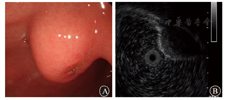

患者女,59岁,因上腹部烧灼感3年余、加重1年于2016年3月1日入院。2013年3月6日的胃镜检查显示慢性浅表性胃炎。2015年7月23日的胃镜检查显示胃体下段前壁有隆起性病变,大小约2.0 cm×2.0 cm,中央溃疡大小约0.5 cm×0.5 cm;病理检查显示慢性重度浅表活动性炎。2016年1月28日的胃镜检查显示胃体、胃窦交界处有隆起性病变,大小约2.5 cm×3.0 cm,中央浅凹溃疡灶大小约0.5 cm×0.6 cm;病理检查显示慢性中度浅表活动性炎。2016年2月18日的CT检查显示胃壁增厚,胃体小弯侧占位(间质瘤不除外),未见肿大淋巴结,见图1。入院后体格检查:体温为36.5 ℃,脉搏为78次/min,血压为130/85 mmHg (1 mmHg=0.133 kPa),一般情况可,未发现明显异常体征。胃镜检查显示胃体下部前壁有2.5 cm×3.0 cm大小的隆起性病变,中央溃疡大小约0.5 cm×0.6 cm,见图2A。超声内镜检查显示病灶处为低回声团块,内部回声欠均匀,起源于固有肌层,向腔外突出,怀疑胃间质瘤,见图2B。患者CEA、CA19-9、CA125等实验室指标均未见异常。排除相关禁忌证后,在全身麻醉下行内镜黏膜下剥离术(endoscopic submucosal dissection,ESD)。病灶周围在黏膜下注射靛胭脂,抬举征阴性;予Dual刀标记并环周切开,见图3A和图3B;继续予Dual刀及末端绝缘刀剥离黏膜及黏膜下病灶,见图3C和图3D;创面予热活检钳电凝止血,术后创面无活动性出血,病灶剥离完整,见图3E和图3F。术后病理显示,黏膜下见一大小约2.2 cm×1.5 cm×1.0 cm的病灶,边界清晰,见图4A;增生的淋巴组织间见散在成巢排列的异型细胞,伴反应性淋巴滤泡形成,见图4B。免疫组织化学检查显示,细胞角蛋白(cytokeratin,CK)5/CK6均阳性,见图5A;P40蛋白质阳性,见图5B;P63阳性;Ki-67为30%;CK7、CK20、CD20、CD3、CD5、CD56、突触素、嗜铬素A、CD34、CD31、CD23和CD21均阴性。原位杂交证实EB病毒感染存在,见图5C。病理诊断为胃淋巴上皮瘤样癌(lymphoepithelioma-like carcinoma,LELC)。与患者充分沟通,行鼻咽镜和全身正电子发射计算机断层显像(positron emission computed tomography, PET)/CT检查排除转移性癌后,接受腔镜下远端胃大部切除术并淋巴结清扫,术后病理示原肿块已切除,符合术后改变,周围未见癌残留,两切端未见癌累及,淋巴结未见癌转移(0/17)。至截稿,患者仍在随访中。